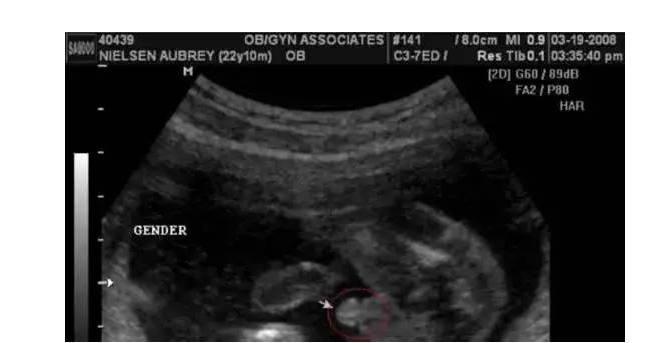

看到红圈里小小的东西了吗?不容易被发现,如果没有人指出,可能准妈妈不一定知道是什么的,但一说出来,就知道了。

"凸出的东西" 是他的标记: 你们看到圆圆的是蛋蛋,如果看到圆圆的加小肠的就是全部丁丁。